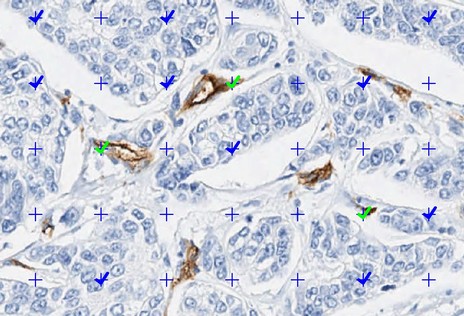

Since 2021, ADCIS has been contributing to the EviRed project, one of the most ambitious RHU projects in ophthalmology. EviRed uses artificial intelligence and multimodal imaging to establish a new classification of diabetic retinopathy in order to improve patient diagnosis, prediction, and treatment:

– Artificial intelligence: combines the deep learning expertise of the LATIM laboratory and ADCIS engineers

– Multimodality: includes ultra-wide field fundus photography, optical coherence tomography, and OCT angiography

– Recruitment of a cohort of 3,000 patients by 12 recruitment centers and follow-up of patients for 2 years

– A dedicated reading center has been created to support the project and annotate the images that will be used to train the deep learning algorithms

The roles of ADCIS and Evolucare in EviRed consist of providing the entire diagnostic process: annotation software, specialized multimodal viewers, deep learning algorithms, and the project’s IT infrastructure